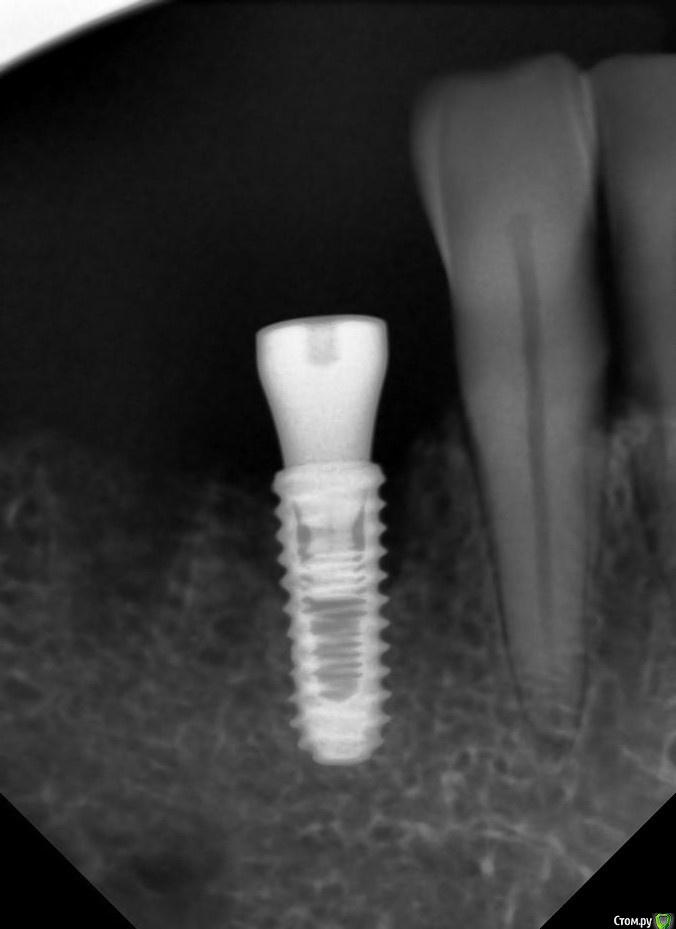

TIGER Опубликовано 5 февраля, 2018 Поделиться Опубликовано 5 февраля, 2018 Подошла пациентка через год после установки ФДМ.определяется выделяемое возле крестального модуля. можно ли вопрос решить местно? мед чистка хлорегексидин перекись ССТ с бугра вестибулярнолибо на удаление имплантата?В связи с последними тендециями, вроде все стараются оставить имплантаты, изменились ли у Вас взгляды?явный периимплантит с чем связываете?откроетесь,будет на половину....в грануляциях,кость не наростёт к сожалению Ссылка на комментарий

kamranchick Опубликовано 6 февраля, 2018 Автор Поделиться Опубликовано 6 февраля, 2018 явный периимплантит с чем связываете?откроетесь,будет на половину....в грануляциях,кость не наростёт к сожалениюя вообще не знаю, ну единственное что с чем могу связывать, на кт в этом месте был пломбировочный материал в кости, какой нибудь йодоформ, ну только с этим могу связывать Ссылка на комментарий

kamranchick Опубликовано 6 февраля, 2018 Автор Поделиться Опубликовано 6 февраля, 2018 Снять формик. Прозондировать. Определить вид дефекта и прогноз. Дальше либо имплантопластика, либо "навынос" и реимплантация.была бы одиночка можно было и не париться, но везде имплантатики стоят, получается если на вынос то еще + 6 месяцев Ссылка на комментарий

kamranchick Опубликовано 9 февраля, 2018 Автор Поделиться Опубликовано 9 февраля, 2018 сверху сьемник так что вариантик с консолькой мне понравился, сегодня воткну.интересно, контамирована поверхность имплантата, и только костное ложе в области 4.4? в области 4.5 все ли будет пучком?) и почему все таки тут он возник этот периимпл? Ссылка на комментарий

kamranchick Опубликовано 9 февраля, 2018 Автор Поделиться Опубликовано 9 февраля, 2018 (изменено) после операции нашел снимок Изменено 9 февраля, 2018 пользователем kamranchick Ссылка на комментарий

dzhancha Опубликовано 10 февраля, 2018 Поделиться Опубликовано 10 февраля, 2018 сверху сьемник так что вариантик с консолькой мне понравился, сегодня воткну.интересно, контамирована поверхность имплантата, и только костное ложе в области 4.4? в области 4.5 все ли будет пучком?) и почему все таки тут он возник этот периимпл?Замечательный ретенционной пункт для зубного налета и бактерий + отсутствие нагрузки. Недавно была пациентка, имплантат без фдм, явилась через 2 года после установки. Убыль кости на 3 витка, также кратером. Ссылка на комментарий

kamranchick Опубликовано 12 февраля, 2018 Автор Поделиться Опубликовано 12 февраля, 2018 В ту же лунку(ложе)не вариант был кстати?можно было бы наверное, но пришлось бы топить, ну и как побаиваюсь я ставить в "инфицированные лунки" Ссылка на комментарий